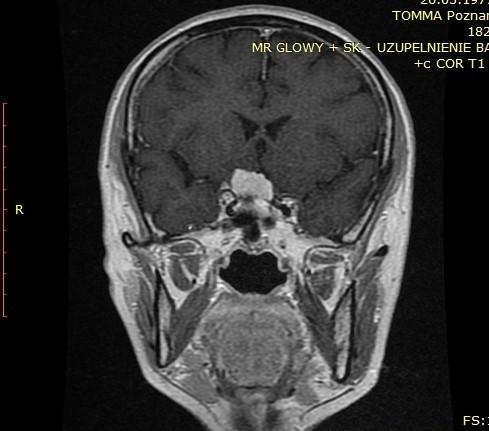

OPONIAKI DUŻYCH ROZMIARÓW I OPONIAKI OLBRZYMIE

Od wielu lat zajmuję się chirurgią oponiaków wewnątrzczaszkowych o różnych lokalizacjach oraz rozmiarach. W grupie operowanych przypadków znalazły się także oponiaki dużych rozmiarów i oponiaki olbrzymie. Guzy te potrafią rosnąć powoli. Wielokrotnie objawy kliniczne przez wiele lat są niespecyficzne - tylko bóle głowy!!! Początkiem przyspieszonej diagnostyki bywa pierwszy w życiu napad padaczkowy. Tak było w grupie prezentowanych przypadków dużych/olbrzymich oponiaków. Wiele z tych guzów pomimo swojej naturalnej łagodności stanowi poważne wyzwanie operacyjne. Operacja oponiaka – to działanie operacyjne wobec guza rosnącego zewnątrzmózgowo, wielogodzinne spokojne oddzielanie i usuwanie „żeby mózg o tym nie wiedział”

Poniżej przedstawiono grupę operowanych pacjentów.

Pacjent pierwszy - Guz usunięty całkowicie, guz łagodny. Pacjent w stanie dobrym, bez objawów neurologicznych – wypisany do domu.

Przed operacją

Tak jak napisałem guzy - oponiaki potrafią rosnąć powoli nie dając żadnych objawów, mózg dostosowuje się do utraty rezerwy wewnątrzczaszkowej dlatego, że proces przebiega powoli. Początkowym objawem był pierwszy w życiu napad padaczkowy. Potem diagnostyka – rezonans magnetyczny i operacja oponiaka. Działanie operacyjne wobec guza rosnącego zewnątrzmózgowo, wielogodzinne spokojne oddzielanie i usuwanie „żeby mózg o tym nie wiedział”

Poniżej prezentacja badan diagnostycznych:

• Ryc 1-7 – badania diagnostyczne przedoperacyjne,

• Ryc 8-13 – badania po operacji.

Pacjentka przyjęta nieprzytomna po napadzie padaczkowym – podczas operacji guz został usunięty całkowicie, miał charakter łagodny. Pacjentka w stanie dobrym, bez objawów neurologicznych – wypisana do domu.